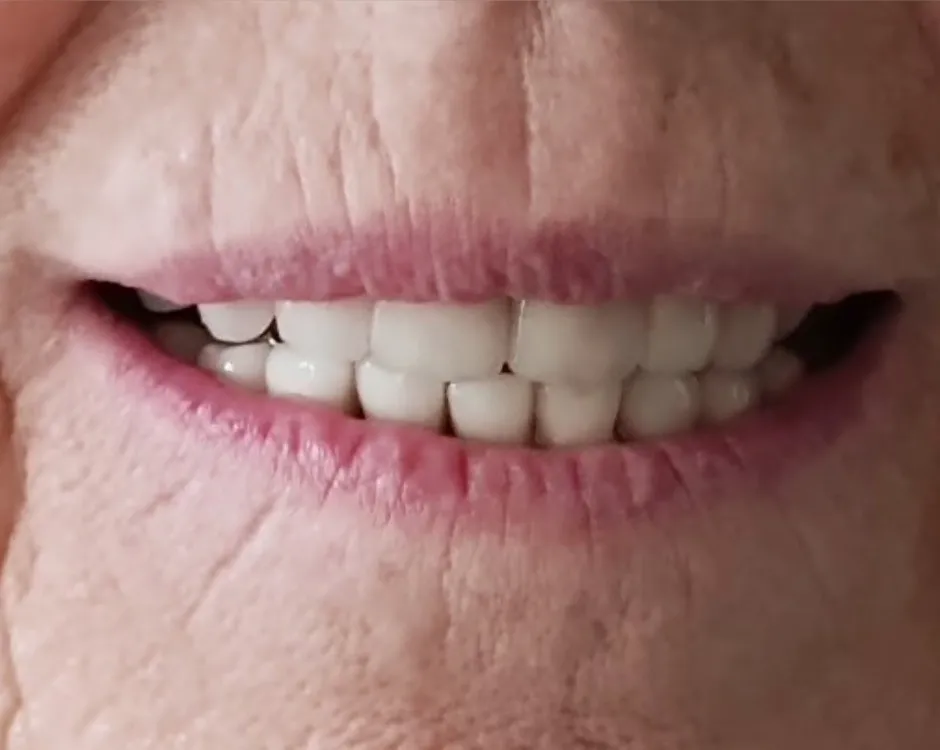

Pani Teresa

Bruksistka